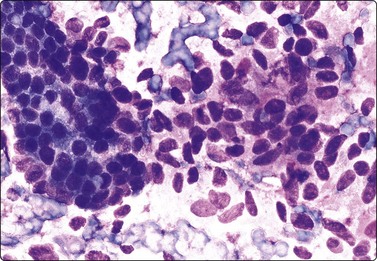

Fig. 4.13 Paraganglioma (atypical)

(A) Smear showing prominent anisokaryosis but a uniformly bland chromatin pattern (MGG, HP); (B) Tissue section of the same case (H&E, IP).

The cytological pattern is suggestive of an endocrine neoplasm and, given the anatomical site, the main differential diagnosis is a thyroid tumor. A follicular arrangement of the tumor cells may suggest a follicular carcinoma, but the fine red cytoplasmic granulation, the characteristic anisokaryosis and the presence of spindle cells closely resemble medullary carcinoma, and this is the main differential diagnosis (Fig. 4.12). Immune markers are helpful. Cells of paraganglioma stain positively for neuroendocrine markers. Staining for calcitonin is negative in most cases, but can occasionally be positive. Cytokeratin, thyroglobulin and TTF1 are negative. Intranuclear cytoplasmic inclusions as in papillary and some other carcinomas of the thyroid can be found in some paragangliomas.50 Knowledge of the exact anatomical site is obviously important. However, paraganglioma can occur in atypical locations including, although rarely, the thyroid. For example, one of our cases diagnosed by FNB had a tumor in the tonsillar region, clinically thought to be a deep parotid tumor (Fig. 4.11); another had a supraclavicular mass diagnosed clinically as lymphadenopathy. Both were histologically confirmed as paragangliomas.

Paraganglioma with a spindle cell pattern can mimic other spindle cell tumors in the neck such as spindle cell medullary carcinoma of thyroid and soft tissue tumors. Nuclear pleomorphism can sometimes be prominent enough to suggest malignancy (Fig. 4.13).5 As in other endocrine tumors, pleomorphism is not a reliable indicator of malignancy, mitotic rate and evidence of necrosis are better related to clinical behavior, and metastasis is the only definitive proof.